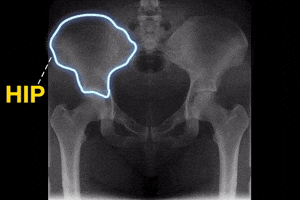

Hip Hip Hooray!